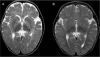

S-Adenosylhomocysteine (AdoHcy) hydrolase deficiency has been proven in a human only once, in a recently described Croatian boy. Here we report the clinical course and biochemical abnormalities of the younger brother of this proband. This younger brother has the same two mutations in the gene encoding AdoHcy hydrolase, and has been monitored since birth. We report, as well, outcomes during therapy for both patients. The information obtained suggests that the disease starts in utero and is characterized primarily by neuromuscular symptomatology (hypotonia, sluggishness, psychomotor delay, absent tendon reflexes, delayed myelination). The laboratory abnormalities are markedly increased creatine kinase and elevated aminotransferases, as well as specific amino acid aberrations that pinpoint the aetiology. The latter include, most importantly, markedly elevated plasma AdoHcy. Plasma S-adenosylmethionine (AdoMet) is also elevated, as is methionine (although the hypermethioninaemia may be absent or nonsignificant in the first weeks of life). The disease seems to be at least to some extent treatable, as shown by improved myelination and psychomotor development during dietary methionine restriction and supplementation with creatine and phosphatidylcholine.